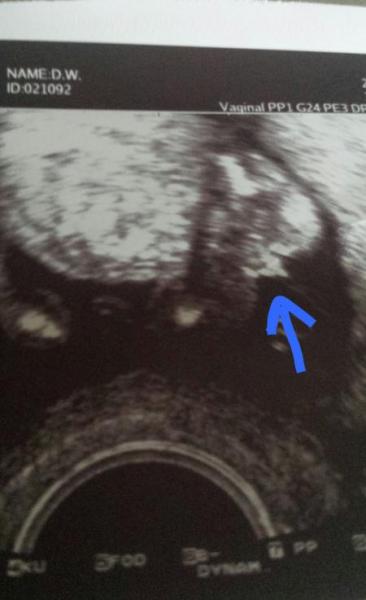

Ich habe sogar ein Ultraschall Bild wo eindeutig zusehen ist das es ein Junge wird Wurde in der 15+6 SSW aufgenommen Was glaubt ihr hat mein FA sich vielleicht verschaut

Bild zu

Hmmm...finde eigentlich auch das es dort doch sehr eindeutig zu sehen ist, dass es suchen um einen kleinen Prinzen handelt... Aber so sah es bei unserem süßen fratz auch sehr früh aus und alle schon "berufserfahrenden Freunde" aus dem Umfeld meinten, dass es auch geschwollene kleine schamlippen sein könnten. Aber wie gesagt, bei uns wird's ein Junge und es sah am Anfang genauso aus.

hm auf dem us-Bild sieht es für mich so gar nicht nach junge aus. bei 15+ war zumindest bei meinem Sohn damals schon ein richtiger Penis zu erkennen. das auf deinem Bild ist ja eher ein Strich, könnte so lange also auch gut die klitoris sein. eine zweitmeinung kannst du dir bestimmt holen wobei ja die Frage ist ob dein zwergi dort zeigefreudiger ist. aber vielleicht geht es dir in ein paar Tagen besser. das man erstmal verwirrt ist finde ich total normal und okay. heißt ja nicht das man sich über das andere Geschlecht nicht genauso freuen kann. irgendwann ;-)